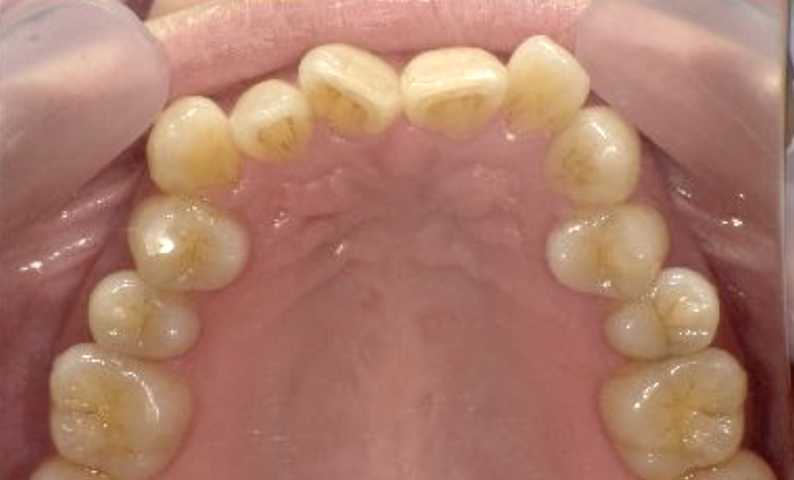

症例_002 上顎だけの部分矯正

治療期間:7ヶ月金額:30万円+税女性前歯のガタガタ上の前歯だけ

| Before | After |

|---|---|

|